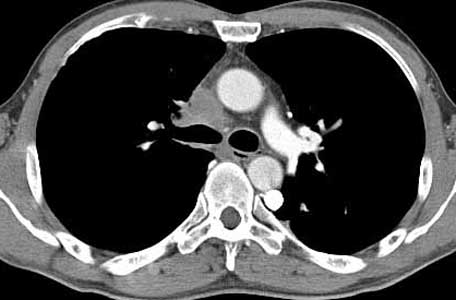

ÀÌÀü¿¡ °áÇÙ °ú°Å·Â ÀÖ´Â ³²ÀÚ 41¼¼·Î CXR ÀÌ»ó ¼Ò°ßÀ¸·Î refer